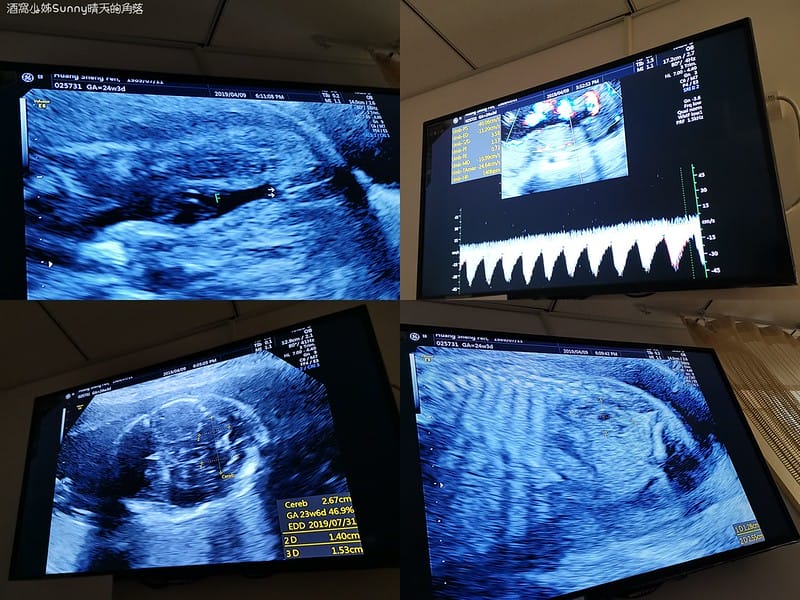

▼回歸正軌.由王醫生親自操做、解說的〈二寶.4D高層次超音波〉正式開始

高層次超音波檢查會看的項目有這些

1. 脊椎(頸椎、胸椎、腰椎、尾椎等)

2. 腦部(顱骨形狀、小腦、大腦側腦室、脈絡叢、透明中膈、後頸皮膚等)

3. 顏面部(眼距、上顎骨、上唇、兩耳、臉部側面輪廓等)

4. 胸部(肺臟、心臟四腔圖、心室出口、肺動脈分支、主動脈弓等)

5. 腹部(胃腸肝膽腎臟膀胱等臟器、橫膈膜、前腹壁、臍動脈數目)

6. 四肢(上臂、前臂、手掌、大腿、小腿及腳掌)

7. 外生殖器

8. 胎盤位置

9. 羊水量

10. 子宮頸長度:不能小於2.5公分 不然胎兒容易早產

11. 彩色都卜勒超音波檢查臍動脈及子宮動脈血流

▼所以醫生在解釋的時候我們大概可以聽懂7~8成(下圖是胎盤,但不說一般人應該很難看懂吧!)

▼這個應該比較好懂!醫生在數寶寶的肋骨一共有12根❤

▼這個是寶寶的腎臟❤

下圖你們猜得出來是在看寶寶的甚麼嗎?

▼答案是:外生殖器,也就是性器官,Abby's二寶是「妹妹」唷~

這是當天妹妹拍到最清楚的4D影像照

▼因為...妹妹全程都用手遮臉,都不給媽咪和阿姨看 >"<